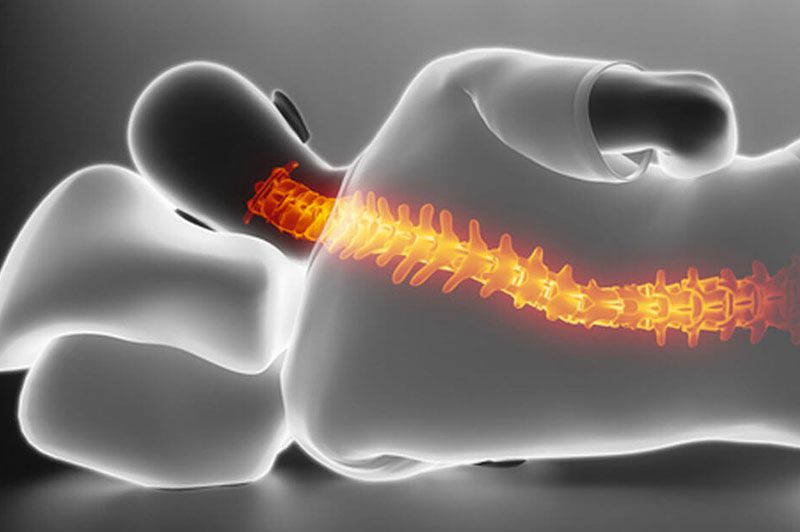

Sleeping Position

Sleeping in an awkward position or with inadequate neck support can lead to neck pain.